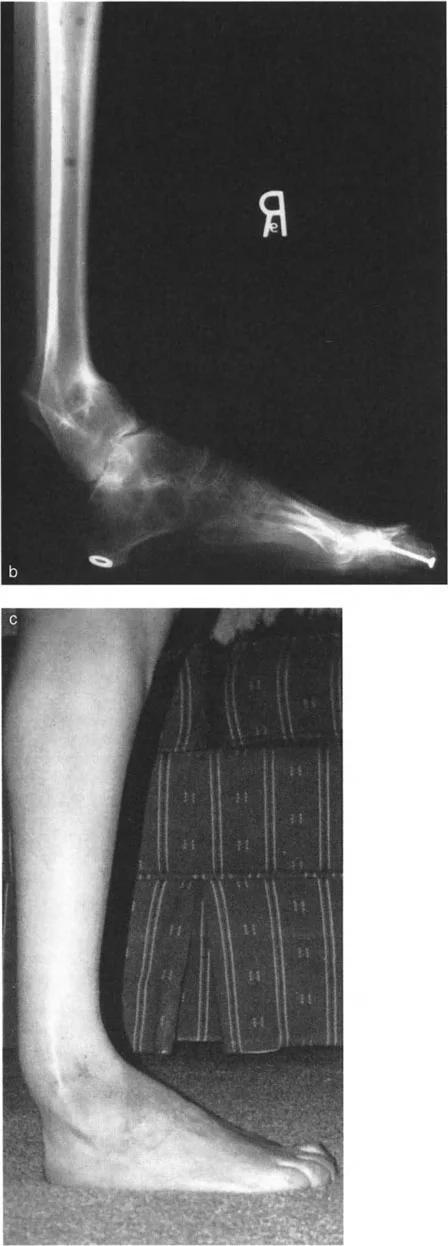

* الأشعة السينية (X-rays) الواقفة لكامل الطرف السفلي: هذه الأشعة ضرورية لتقييم المحاذاة الكلية للطرف السفلي تحت تأثير وزن الجسم. يطلب الأستاذ الدكتور محمد هطيف صورًا شعاعية كاملة الطول للساق أثناء الوقوف (Full-length standing alignment films) لتقييم المحور الميكانيكي للساق وتحديد زوايا المفاصل بدقة.

* الأشعة السينية الجانبية والامامية الخلفية للكاحل: تُظهر هذه الصور تفاصيل مفصل الكاحل نفسه، بما في ذلك زاوية القصبة الأمامية البعيدة (ADTA) وزاوية القصبة الوحشية البعيدة (LDTA)، وهي زوايا حاسمة لتحديد التشوه في المستويين الأمامي والسهمي.

* منظر سولتزمان (Saltzman View): هذا المنظر الإشعاعي الخاص يتم الحصول عليه بزاوية 20 درجة لقياس محاذاة عظم العقب (Calcaneus) بالنسبة لقصبة الساق، وهو أمر بالغ الأهمية لتقييم تعويضات القدم الخلفية.

تغير شكل القدم والكاحل

• تشوه مرئي: في كثير من الحالات، يكون التشوه واضحًا للعين المجردة. قد يظهر الكاحل منحرفًا إلى الداخل (تقوس) أو إلى الخارج (روحبة).

• تشوه التقوس (Varus): يبدو الكاحل والقدم منحرفين إلى الداخل، مما يجعل القدم تبدو ذات قوس عالٍ (قدم جوفاء). هذا يسبب ضغطًا زائدًا على الحافة الخارجية للقدم.

• تشوه الروحبة (Valgus): يبدو الكاحل والقدم منحرفين إلى الخارج، مما يؤدي إلى تسطح قوس القدم (قدم مسطحة مرنة). هذا يزيد الضغط على الجانب الخارجي لمفصل الكاحل.